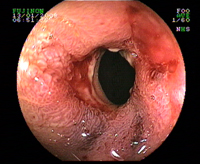

Sténose esophagienne peptique